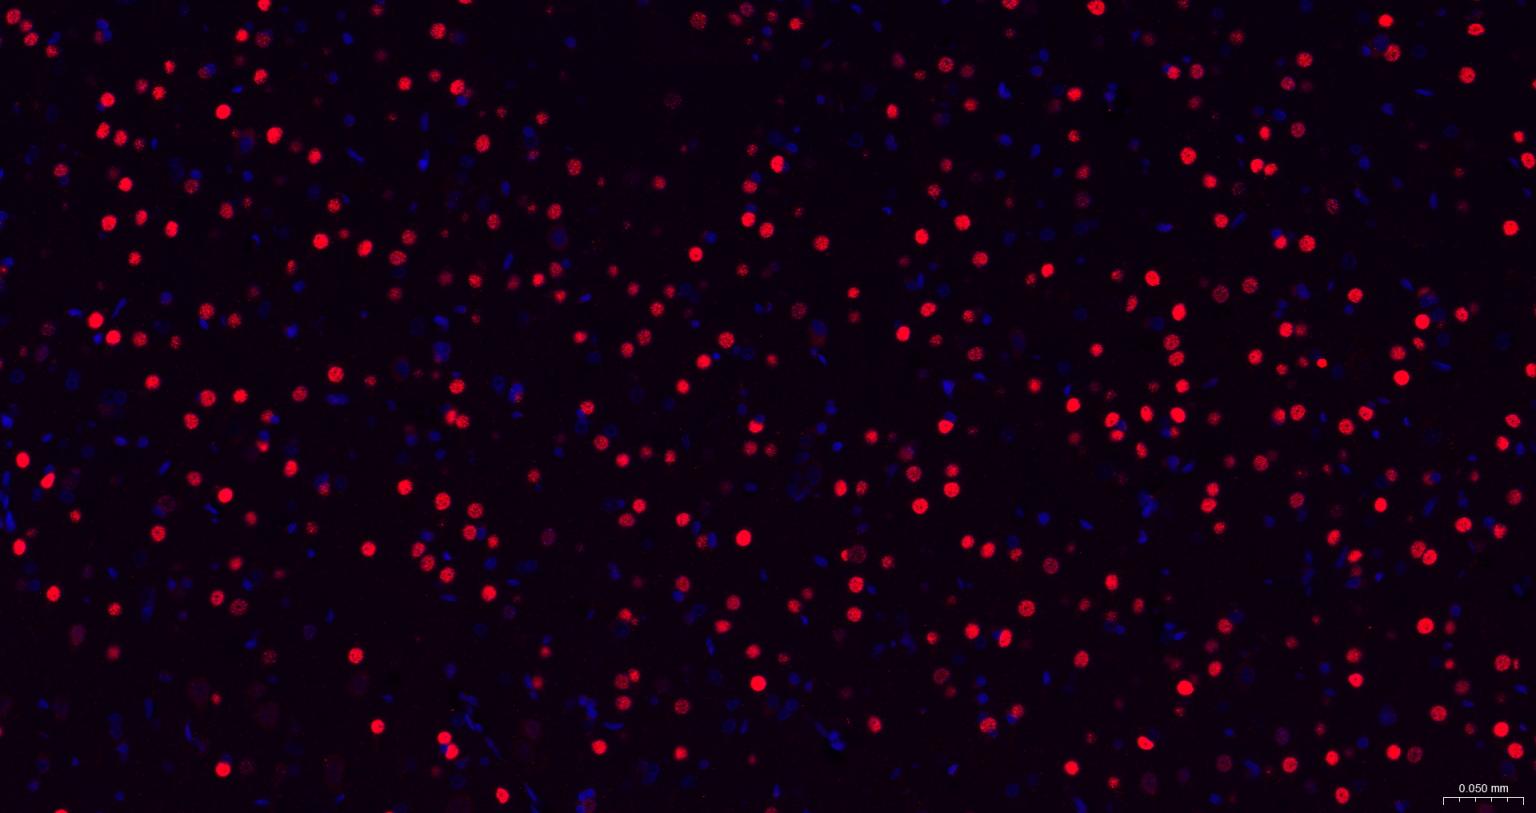

IHC-PHuman, Mouse, Rat1:100-500

IHC-FHuman, Mouse, Rat1:100-500

IFHuman, Mouse, Rat1:100-500